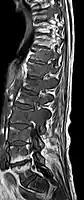

- Comparaison scanner/IRM pour des métastases ostéolytique d'un cancer du sein dans la colonne vertébrale

Scanner sagittal reconstruit, représentation dans la fenêtre osseuse. Comme la patiente avait des métastases dans toutes les régions du corps, elle ne pouvait pas lever les bras pour l'examen, ce pourquoi les mains sont présentées.

Scanner sagittale, parties molles. Outre les métastases dans la colonne vertébrale, qui envahissent en partie le canal médullaire vers l'arrière, métastases aussi dans le sternum. Plus des métastases dans le foie.

IRM natif avec pondération T1.

IRM sagittal natif avec pondération T1. On voit clairement l’extension jusqu'aux lames vertébrales.